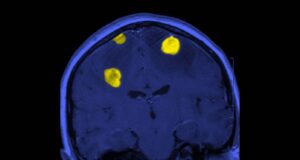

Dan esperanza a pacientes con tumores cerebrales

Los tumores cerebrales ocupan el lugar 19 entre todas las neoplasias, y el 10 entre las más letales. A nivel mundial, cada año se...